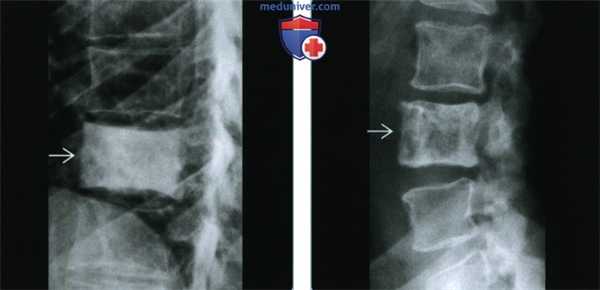

(Слева) Рентгенография грудного отдела позвоночника в боковой проекции: определяется классический «мраморный» позвонок с плотной костью, замещающей тело позвонка целиком, но без изменения его размеров. Очаговый склероз, как на этом изображении, характерен для мастоцитоза.

(Справа) Рентгенография в боковой проекции, этот же пациент: определяются смешанный лизис и склероз, а также увеличение позвонка. Такие признаки могут свидетельствовать о болезни Педжета, но в данном случае это полиоссальный мастоцитоз. Рентгенологическая картина при этом диагнозе сбивает с толку, поскольку может иметь вид, характерный для остеопении, склероза или смешанной формы заболевания.